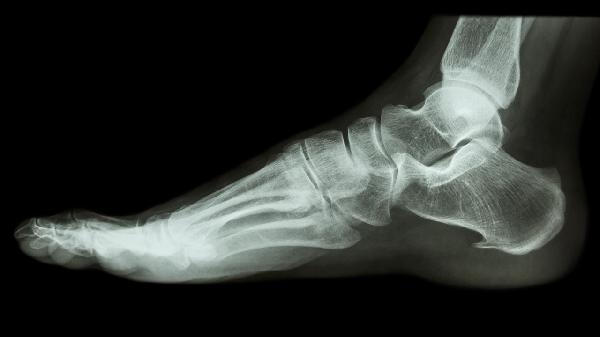

骨裂的主要癥狀包括局部疼痛、腫脹、活動受限,嚴重時可能出現(xiàn)瘀斑或畸形。疼痛在活動或受力時加劇,休息后緩解,X線檢查可確診。

2. 腫脹和瘀血因局部軟組織損傷和毛細血管破裂導致,通常在傷后24小時內(nèi)逐漸明顯。腳踝骨裂可見踝關(guān)節(jié)周圍彌漫性腫脹,皮膚發(fā)青;指骨骨裂可能伴隨甲床下瘀斑。冰敷和抬高患肢能緩解腫脹。

疑似骨裂應(yīng)避免患處受力,使用夾板或支具臨時固定,盡快就醫(yī)拍攝X光或CT。治療方式包括石膏固定4-6周、手術(shù)內(nèi)固定(如鋼板、螺釘或髓內(nèi)釘),配合鎮(zhèn)痛藥(布洛芬、對乙酰氨基酚)和鈣劑??祻推谛铦u進式鍛煉,如腕部骨裂可做握力球訓練,下肢骨裂需拄拐避免過早負重。